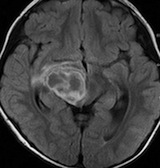

放射線治療後7週目

フレア画像です。腫瘍サイズが増大しています。もともと腫瘍周辺浮腫はなかったのですが大脳基底核と視床に浮腫が出現しています。スード・プログレッションの始まりです。

放射線治療後9週目

フレア画像です。たった2週間で脳浮腫が高度の脳浮腫となっています。失語症と右片麻痺と認知機能低下が生じました。ステロイド剤とグリセリンの点滴を行いました。